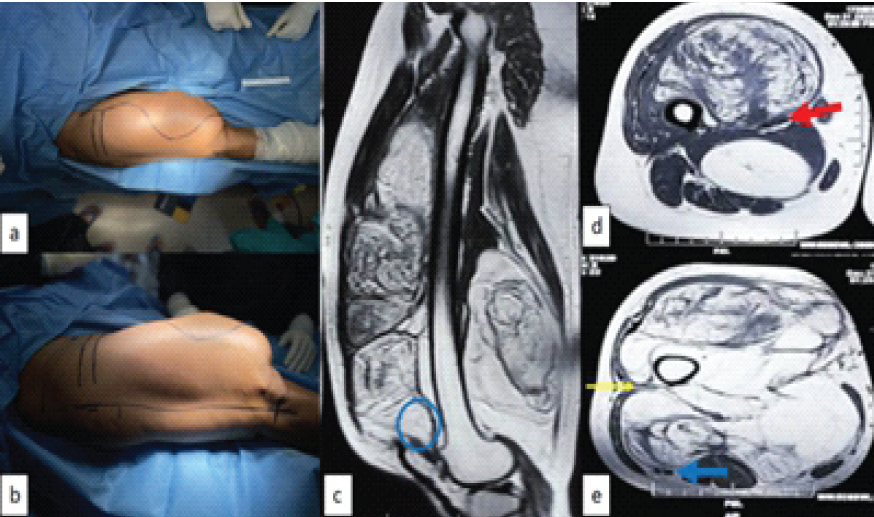

A 63-year-old female presented with huge, painless swelling in thigh (Fig. 1).

Figure 1: Intraoperative picture of thigh and pre-operative magnetic resonance imaging (MRI); (a) superior view showing medial incision sacrificing medial skin and islanding out all previous surgical and biopsy scars, (b) lateral view showing lateral incision, (c) MRI with sagittal image showing proximity to femur and tumor extent up to suprapatellar pouch (blue round), (d) axial section through proximal part of tumor showing vessels (red arrow) lying between two parts of the tumor, and (e) axial section through distal part showing vicinity of tumor with sciatic nerve (blue arrow) and only virgin plane (yellow arrow) through which femur can be reached.

She had history of excision of mass 8, 4, and 2 years back. All post-surgery specimens were reported as ALT/well-differentiated liposarcoma (ALT). She underwent radiological investigation in form of local radiograph and magnetic resonance imaging (MRI). On radiograph, tumor was scalloping femur cortex without involving it. On MRI, it measured 147 × 102 × 263 mm (antero-posterior × transverse × cranio-caudal) and it was involving all compartments of thigh, femoral vessels, and encircling femur almost 360° at some places. Computed tomography (CT) scan was done, in addition, to confirm that there was no erosion of femur cortex. Patient had two previous surgical scars. Biopsy was done from most heterogeneous area on MRI which was reported as well-differentiated liposarcoma. Systemic staging was done in form of ultrasound of bilateral groin and high-resolution CT thorax which did not show any disease [4].

First on medial side, fusiform incision islanding out previous surgical and biopsy scars. Second on lateral aspect, straight on lateral intermuscular septum (Fig. 1).

Part of superficial femoral vessels inside the tumor (Fig. 1) to be sacrificed and reconstructed with polytetrafluoroethylene (PTFE) graft. Profunda femoris to be sacrificed without reconstruction.

Sciatic nerve to be saved (Fig. 1).

Periosteum of femur will be taken as margin at all sites, where tumor is close to the bone (Fig. 1).

Patient positioned supine on table and supported from all sides to allow maximum tilting of the table to facilitate exposure of thigh from all sides. Skin incisions marked as described in planning (Fig. 1). Bony prominence, that is, greater trochanter, lateral joint line, and patella, was identified and marked for measurement.